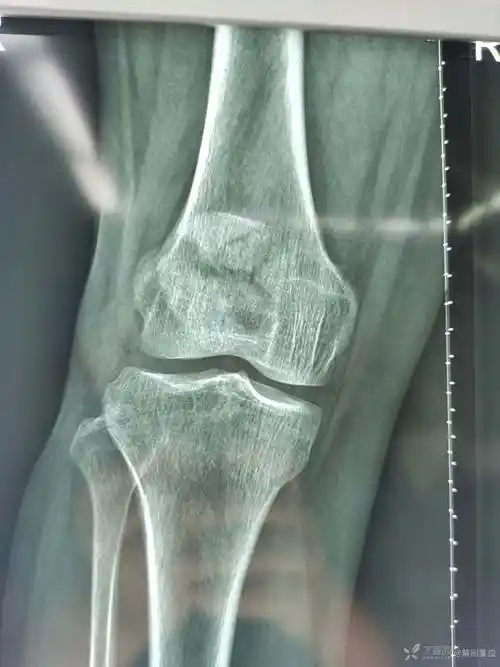

分享一例髌骨骨折